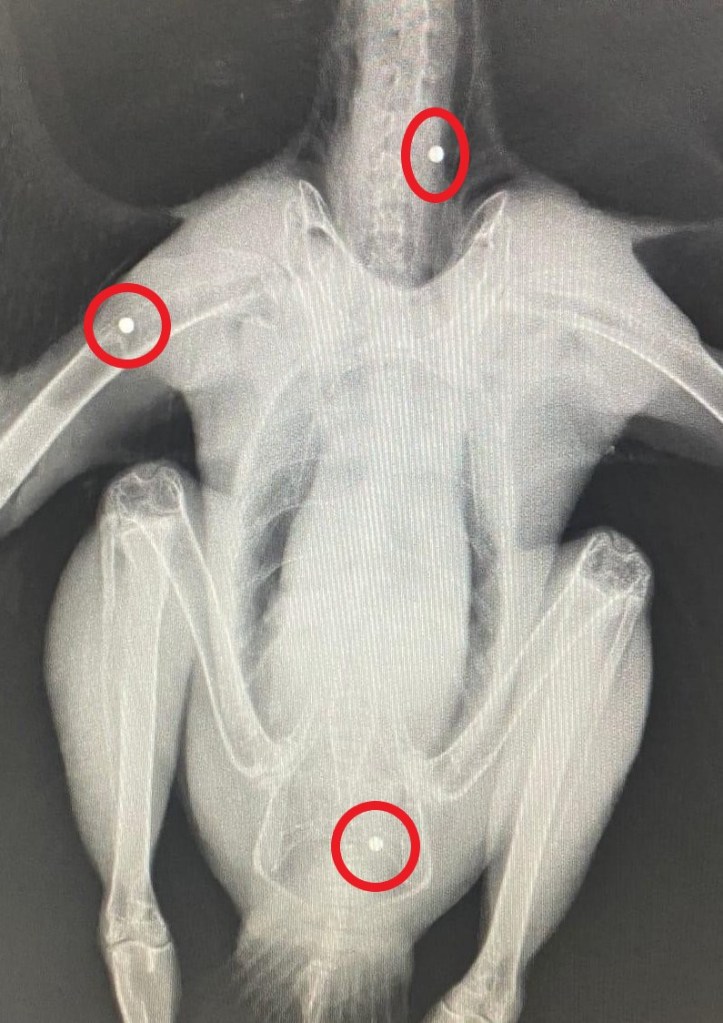

The buzzard that was found shot in Colchester, Essex, earlier this month has unfortunately not survived its injuries.

It was found on 11th January 2023 near to Hardy’s Green and Heckford Bridge and was picked up by a member of the public.

The buzzard had suffered a broken wing and internal injuries and was being cared for by professionals at Colchester Owl Rescue. It succumbed to its injuries over the weekend.